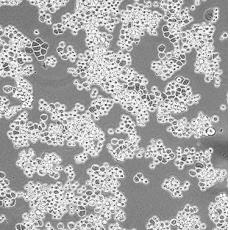

產品名稱 MDA-MB-453

中文名稱 人乳腺癌細胞

組織來源 乳腺腺癌;胸腔積液轉移;女性

生長特性 adherent

形態特征 epithelial

細胞描述 該細胞系由CailleauR在1976年從一名48歲的患有轉移性乳腺癌的白人女性的心包滲出液中分離建立的。該細胞表達FGF的受體。